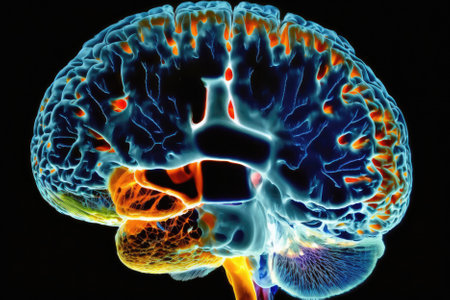

Brain activity, neural impulses in the human brain. the neurobiological concept

Sochi, Russia 20.02.2022: 3d model of the movement of nerve impulses in the human brain.

This close-up image of the human brain captures neurons firing and neural extensions in stunning detail, revealing the intricate web of connectivity that underpins thought, memory, and all

This close-up photo captures the intricate details and structures of a human brain, Cross-sectional image of a human brain, AI Generated

A Fmri Scan Of A Brain During Rest